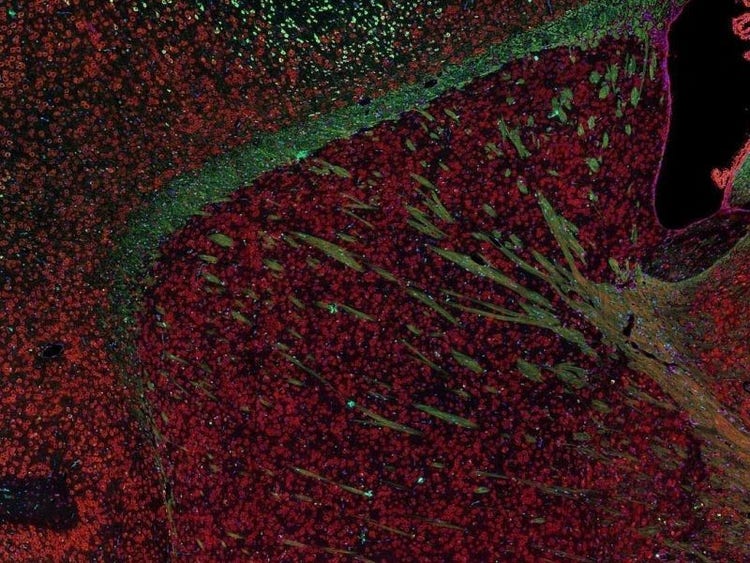

Fluorescence imaging of a mouse brain

Cette vue d’un cerveau de souris est en réalité constituée par l’assemblage d’une multitude d’images prises par imagerie de fluorescence.

Le scientifique britannique Sir George G. Stokes a d’abord constaté que la fluorine minérale devenait fluorescente lorsqu’elle était éclairée par une lumière ultraviolette, et il a inventé le mot « fluorescence ». Stokes a remarqué que la lumière fluorescente présentait des longueurs d’onde supérieures à celles de la lumière d’excitation, un phénomène aujourd’hui connu sous le nom de « déplacement de Stokes ». La microscopie de fluorescence est une excellente méthode pour étudier une matière qui peut devenir fluorescente soit sous sa forme naturelle (appelée fluorescence primaire ou autofluorescence), soit lorsqu’elle est traitée avec des produits chimiques qui peuvent devenir fluorescents (appelée fluorescence secondaire).